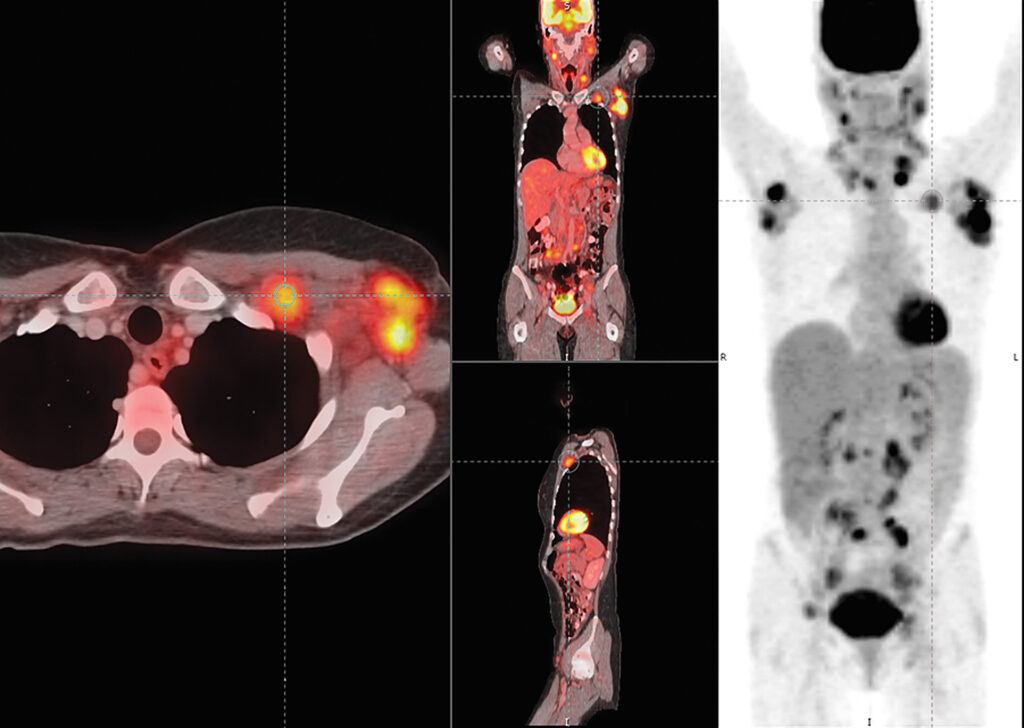

Mirada Oncology Fusion™

Mirada Oncology Fusion is a multiple modality software application for the evaluation of oncologic disease. Mirada’s XD3 platform provides a full suite of practical applications for solving your departmental multi-modal image viewing needs.